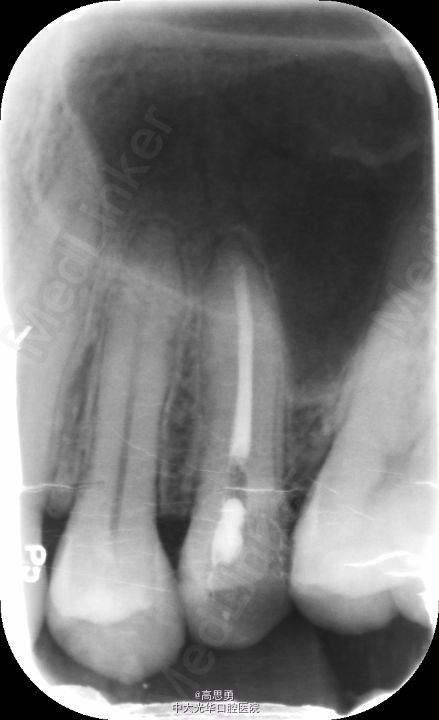

#25去腐未尽穿髓,行根管治疗。根充后X线片示:根充止点距解剖根尖孔约2mm。怀疑欠充,遂掏出牙胶后重新测量工作长度、重新根备后进行充填。第二次充填X线片与之前类似。认为可能是解剖根尖孔与生理根尖孔的差异所导致,玻璃离子暂封,观察。